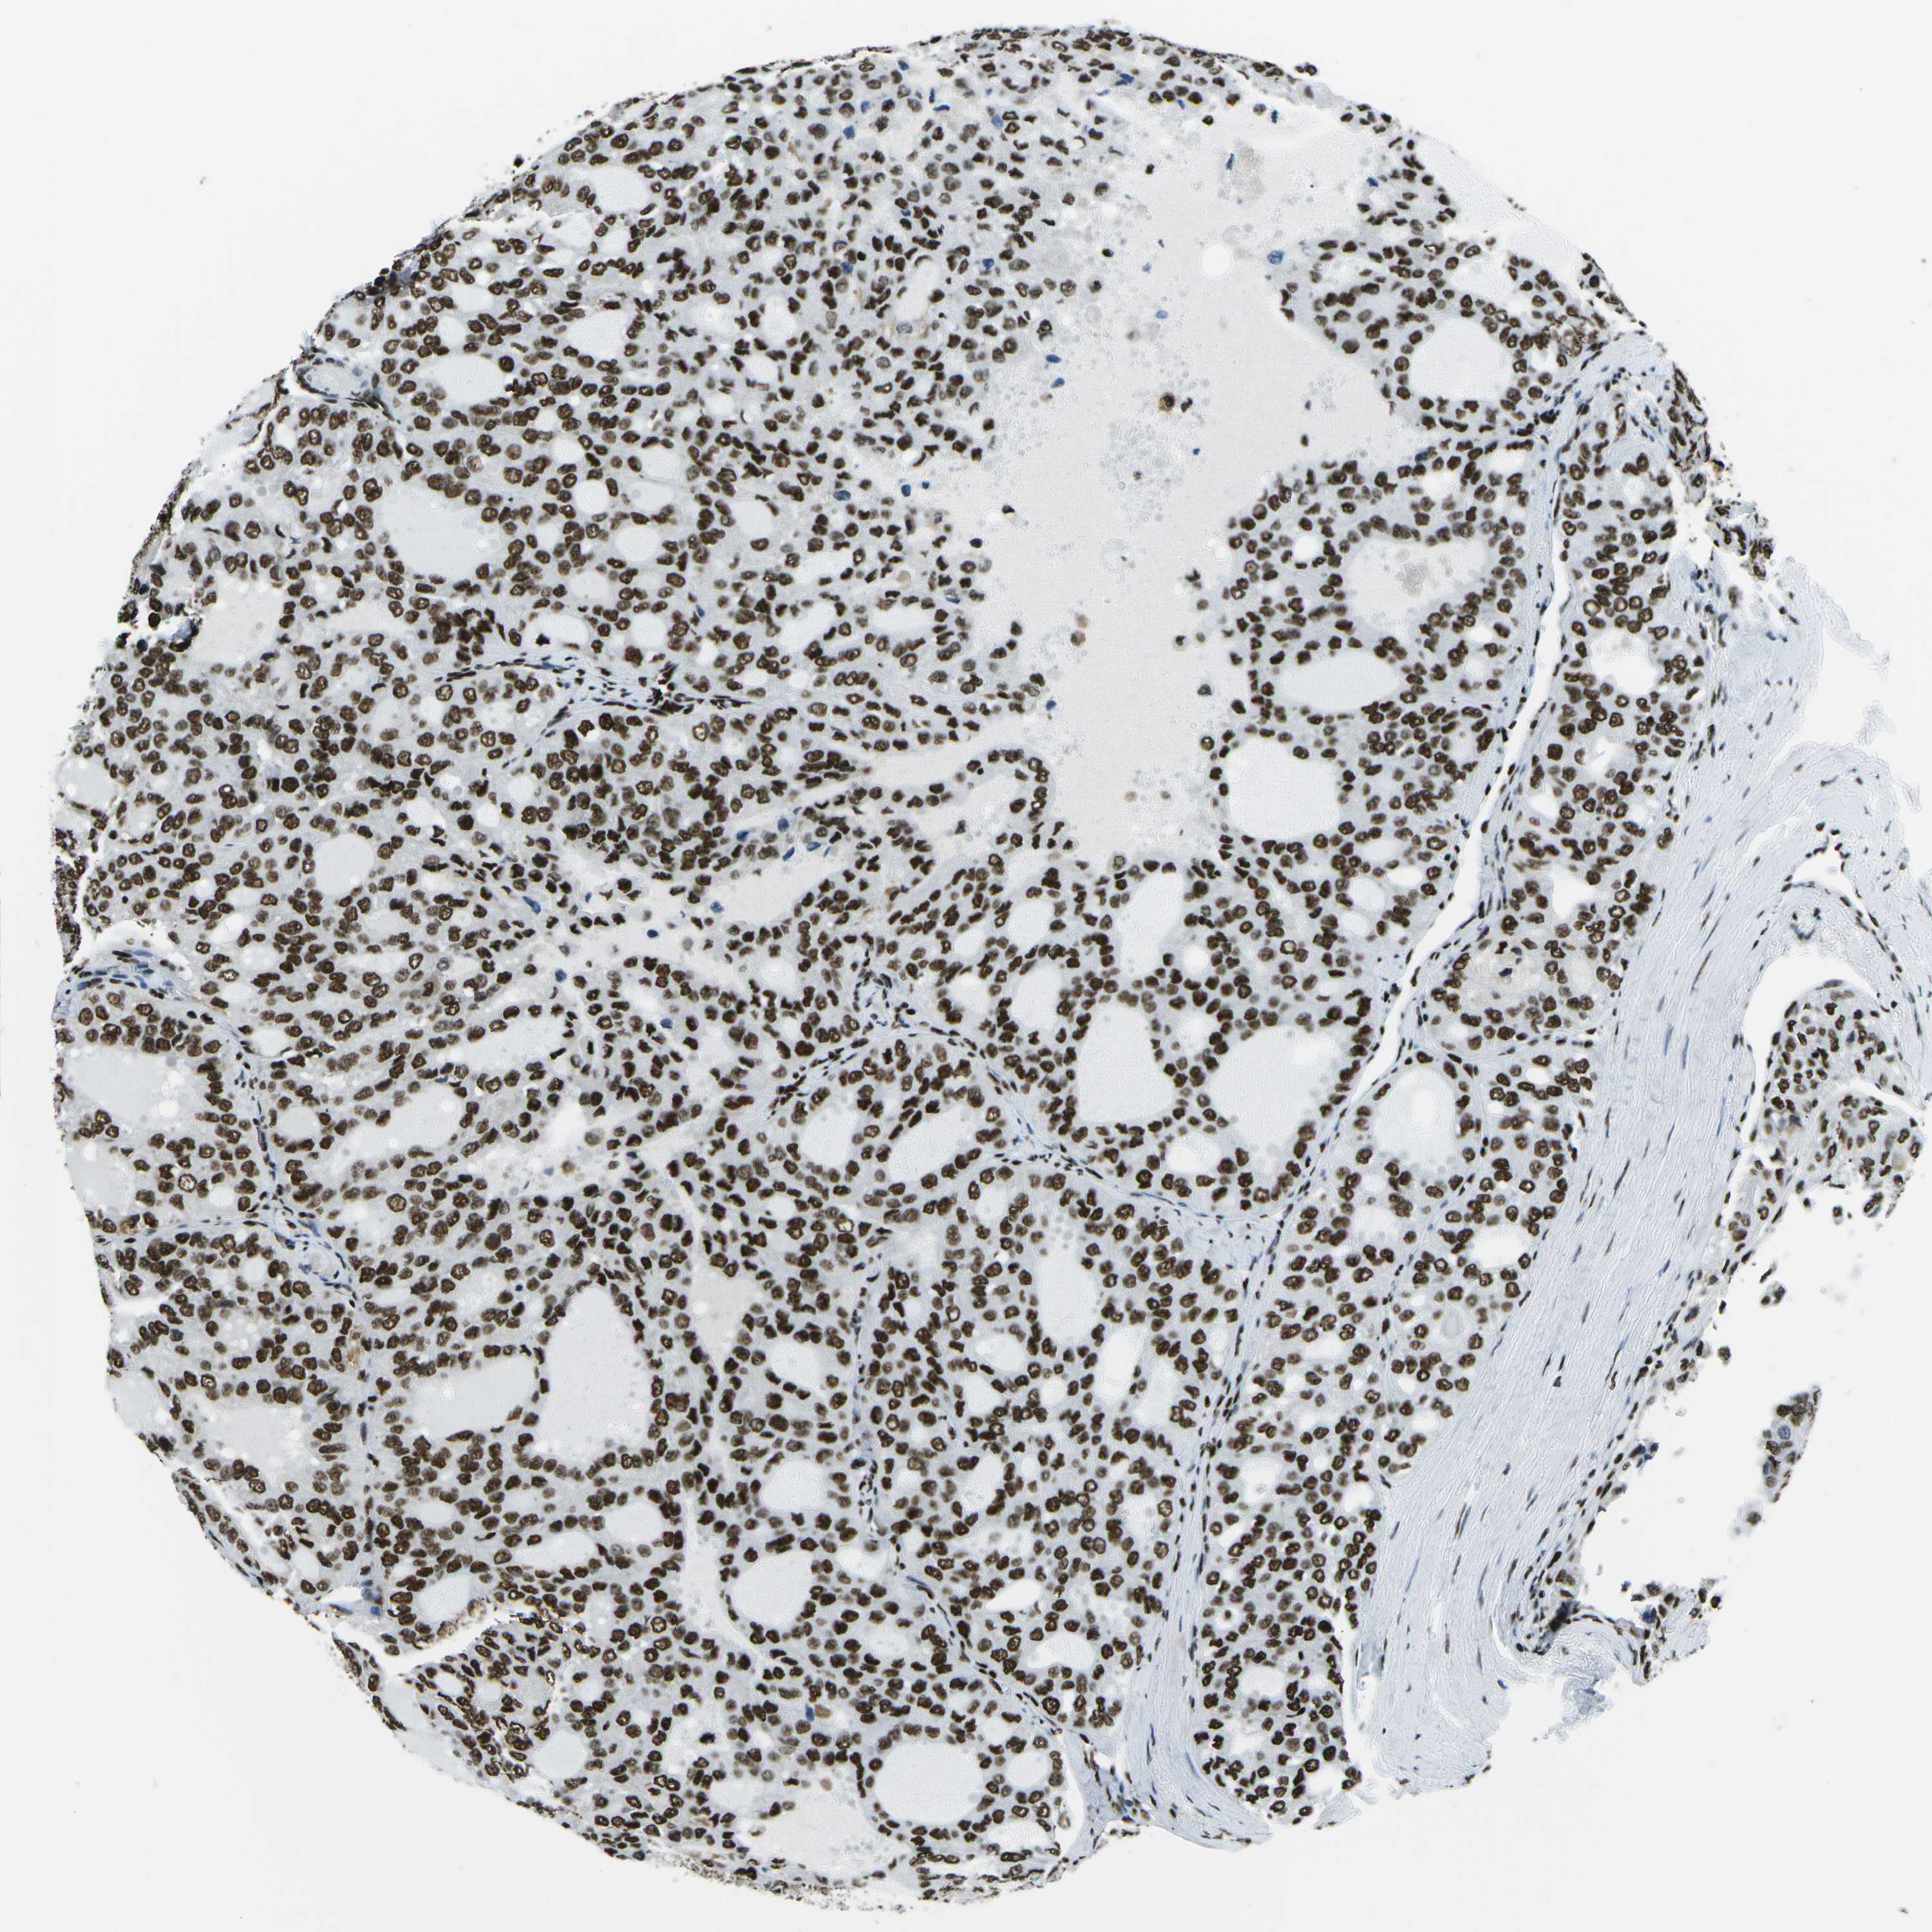

THYROID CANCER - Protein expressioni

A mouse-over function shows sample information and annotation data. Click on an image to view it in a full screen mode. Samples can be filtered based on level of antibody staining by selecting one or several of the following categories: high, medium, low and not detected. The assay and annotation is described here.

Note that samples used for immunohistochemistry by the Human Protein Atlas do not correspond to samples in the TCGA dataset.

Antibody stainingi

Antibody staining in the annotated cell types in the current human tissue is reported as not detected, low, medium, or high, based on conventional immunohistochemistry profiling in selected tissues. This score is based on the combination of the staining intensity and fraction of stained cells.

Each image is clickable and will lead to virtual microscopy that enables deeper exploration of all samples and also displays staining intensity scores, fraction scores and subcellular localization as well as patient and tissue information for each sample.

Antibody HPA051748

Antibody HPA052661

Antibody CAB016326

Staining

High

Medium

Low

Not detected

Intensity

Strong

Moderate

Weak

Negative

Quantity

>75%

75%-25%

<25%

None

Location

Nuclear

Cytoplasmic/membranous

Cytoplasmic/membranous,nuclear

Papillary adenocarcinoma, NOS

Follicular adenoma carcinoma, NOS